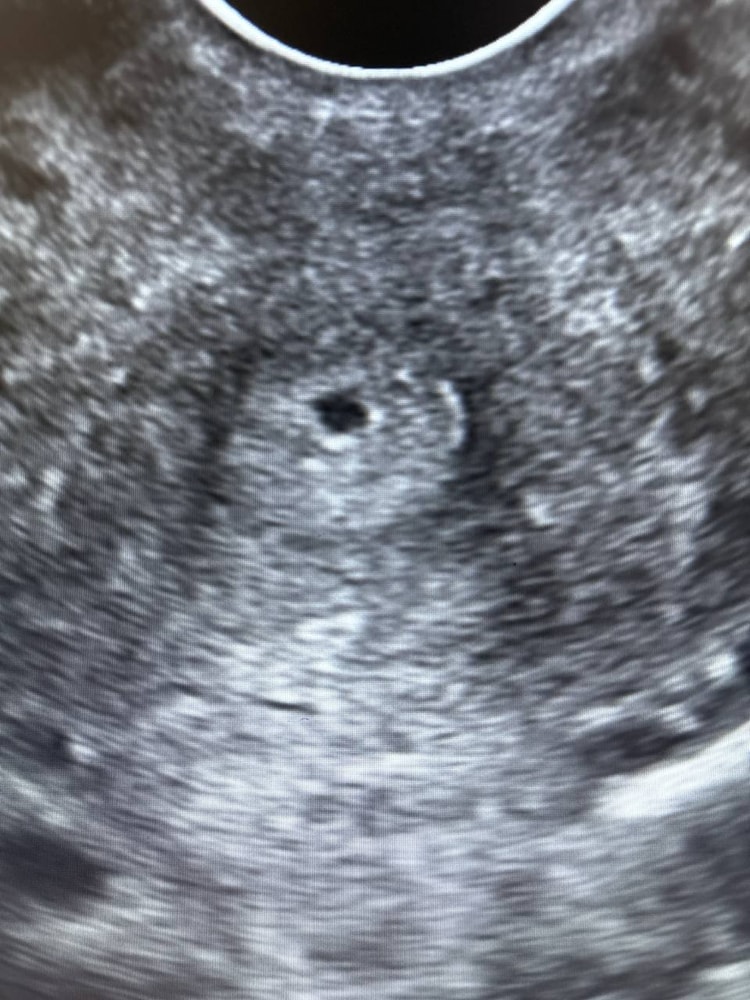

Это совсем не похоже на плодное яйцо.

Раздвоение Птичности, сказали что похоже очень ,и желтое тело у меня и хороший эндометрий

Елизавета, сказали либо пя либо скопление жидскости